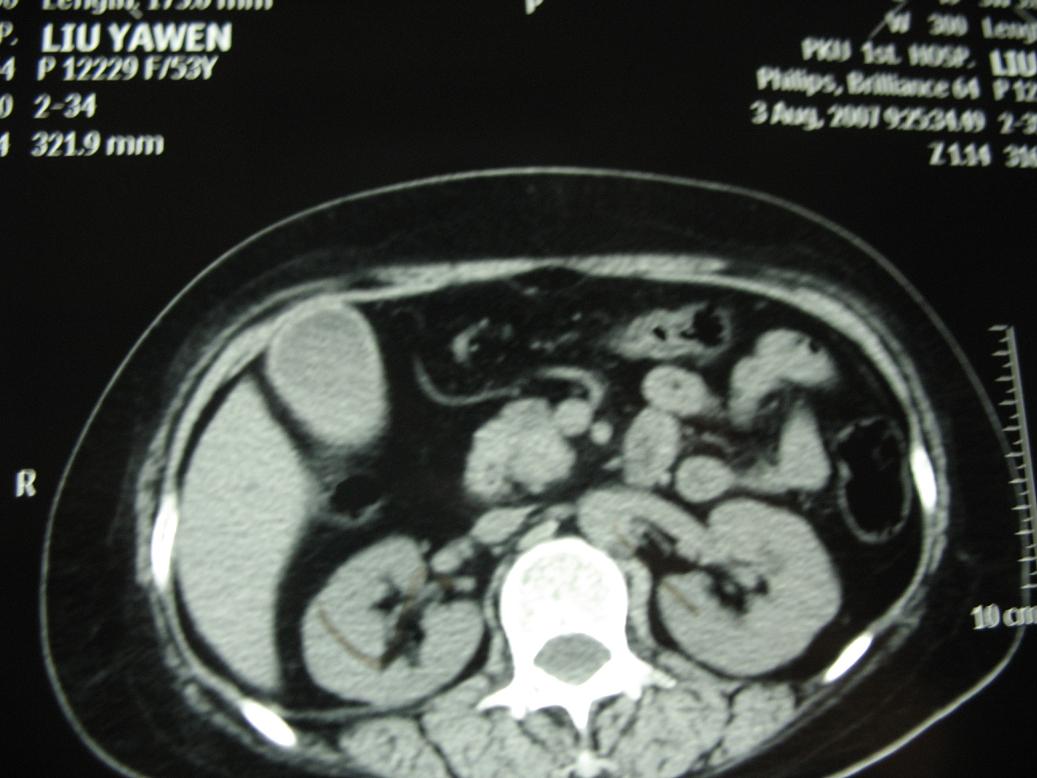

标题: CT17151:女 53岁 腹痛数月余 轻微黄疸 [打印本页]

女 53岁 腹痛数月余 轻微黄疸

1)考虑胰头癌。2)胆囊炎。

壶腹周围占位(钩突ca?)

胰腺钩突mt

支持胰腺钩突ca伴胆系梗阻,胆囊炎

考虑 胰头癌可能性大。